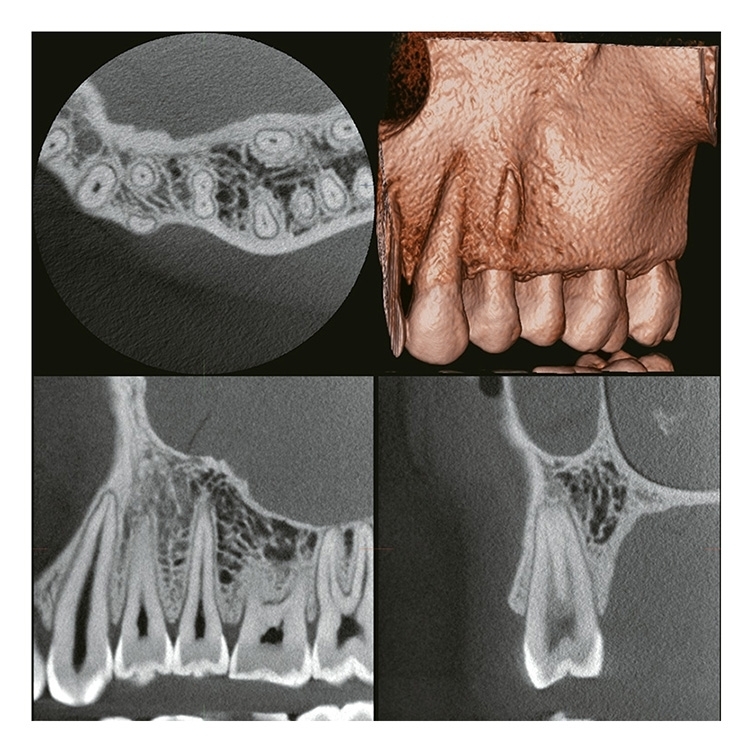

2 VERAVIEW (X800)_CP S(F40) M(R100) L(F150)

Information / DemoPanorama 3D - FOV Up bis zu: Ø 150 X H 140

Ø 40 x H 40, Ø 40 x H 80

(R100) M

Ø 40 x H 40, Ø 40 x H 80

Ø 80 x H 40, Ø 80 x H 50, Ø 80 x H 80

R 100 x H 40, R 100 x H 50, R 100 x H 80

(F150) L

Ø 40 x H 40, Ø 40 x H 80

Ø 80 x H 40, Ø 80 x H 50, Ø 80 x H 80

R 100 x H 40, R 100 x H 50, R 100 x H 80

Ø 150 x H 50, Ø 150 x H 75, Ø 150 x H 140